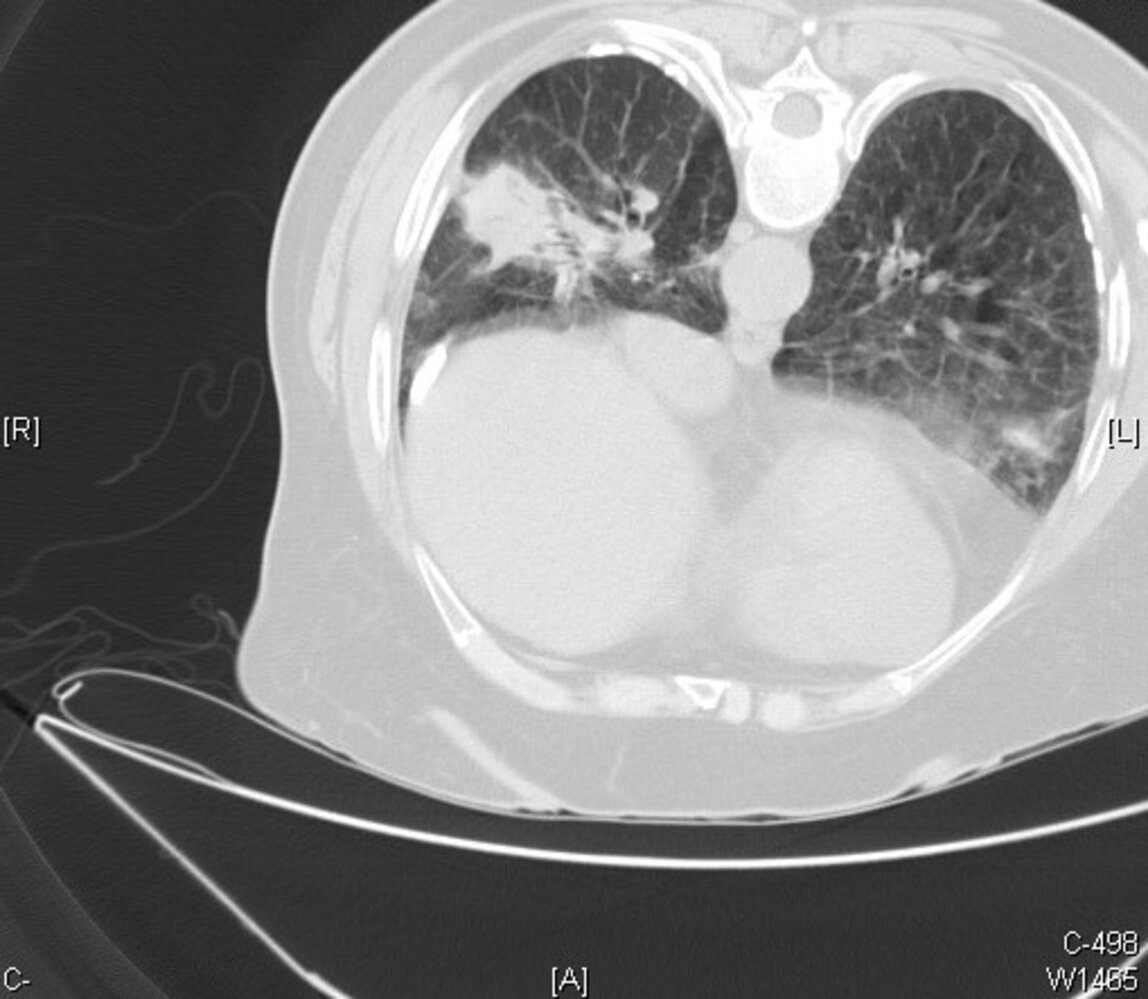

• HRCT

• Signs of interstitial fibrosis, e.g.:

• Subpleural linear opacities

• Septal and interlobular thickening

• Honeycombing

• Rounded atelectasis

• Pleural abnormalities

• Calcified (ivory white) or noncalcified pleural plaques

• Pleural reticulonodular opacities

• Pleural thickening